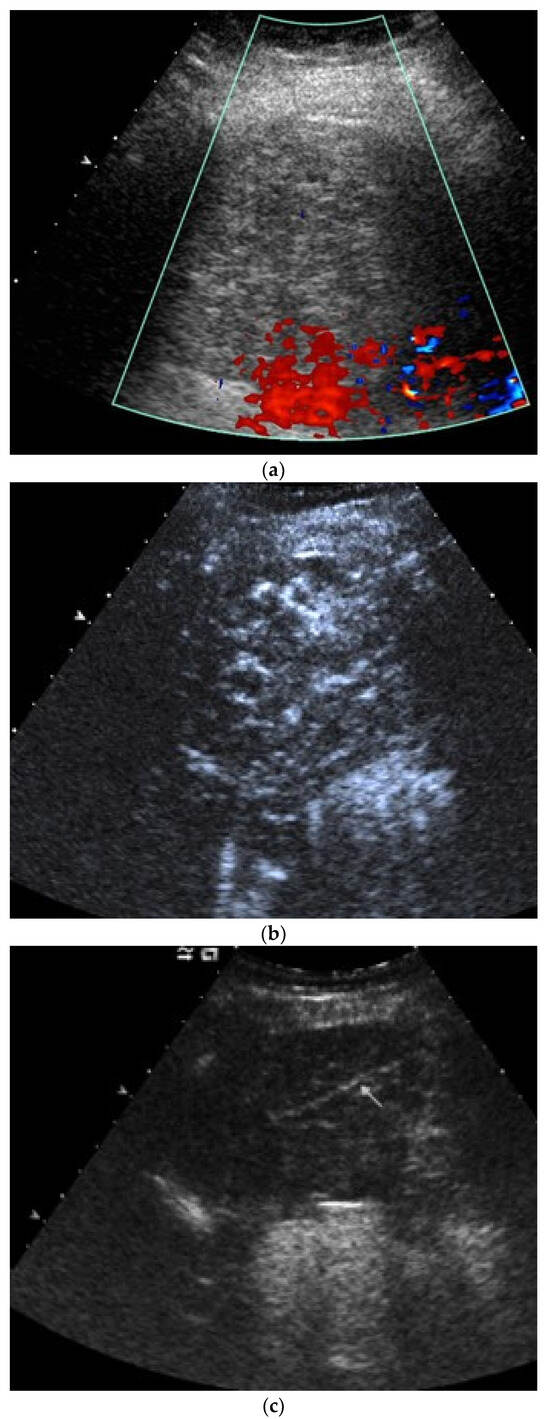

| Empyema | Hypoechoic thickened pleura, internal echos in the pleural effusion, hypoechoic pus, hyperechoic gas reflexes, fibrin strands, and chambering. In the phase of organization, thickened pleura, chambering of the pleural space. |

| Empyema necessitans | Exceeds the parietal pleura and infiltrates the surrounding soft tissue and chest wall muscles. |

| Tuberculous pleuritis | Pleura effusion with fibrin strands, pleural calcification, and thickening. Hypoechoic granulomatous inflammation and granulomas with hyper-enhancement on CEUS in thickened pleura. Hypoechoic caseous abscesses in thickened pleura, hypo- or nonenhanced, heterogeneously enhanced lesions, with contrast-enhanced septations and contrast-enhanced rim. |